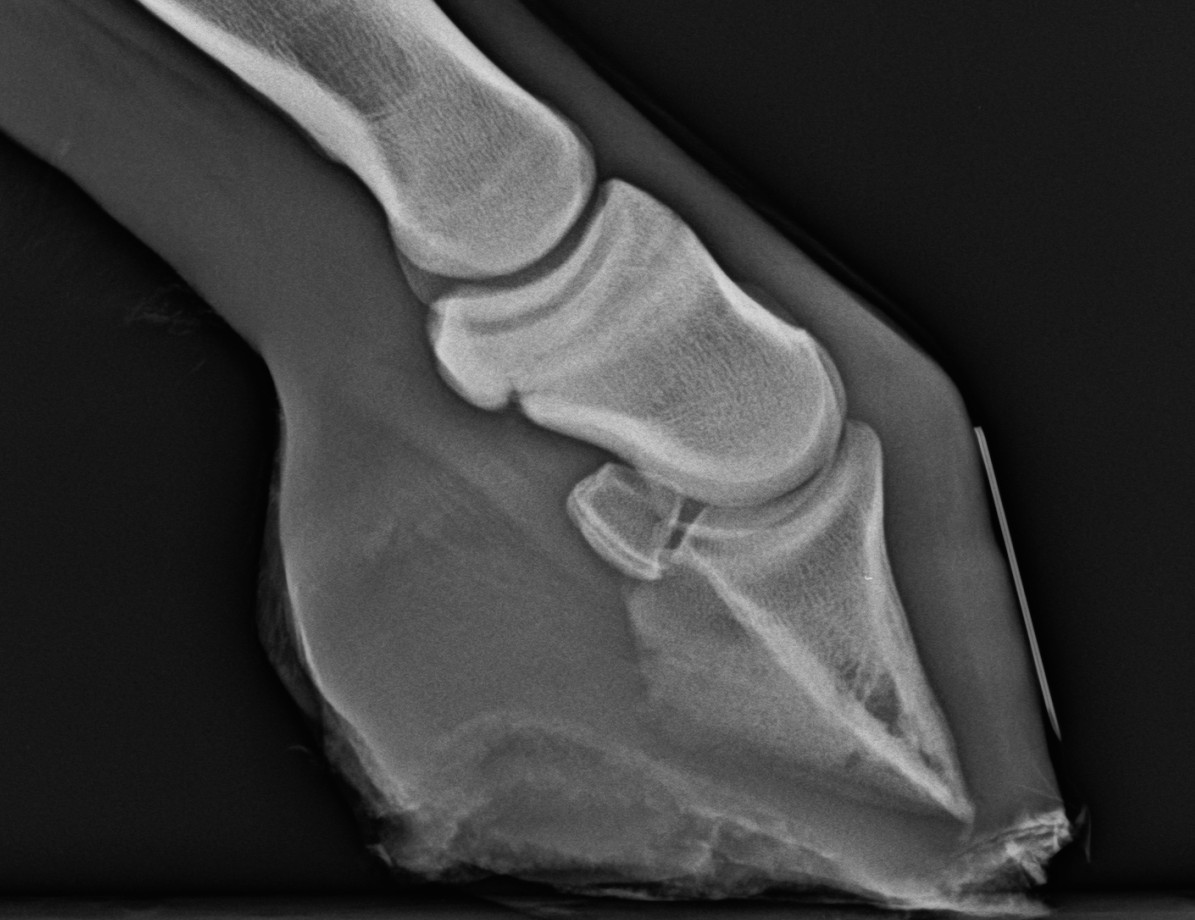

A diagnózis nem nehéz, de RTG vizsgálatot szoktunk végezni.

Fiatal, bakpatás csikó. A pataízület hajlított állapotban. A hegyfali szaru erősen elkopott, egyéb probléma még nem alakult ki.